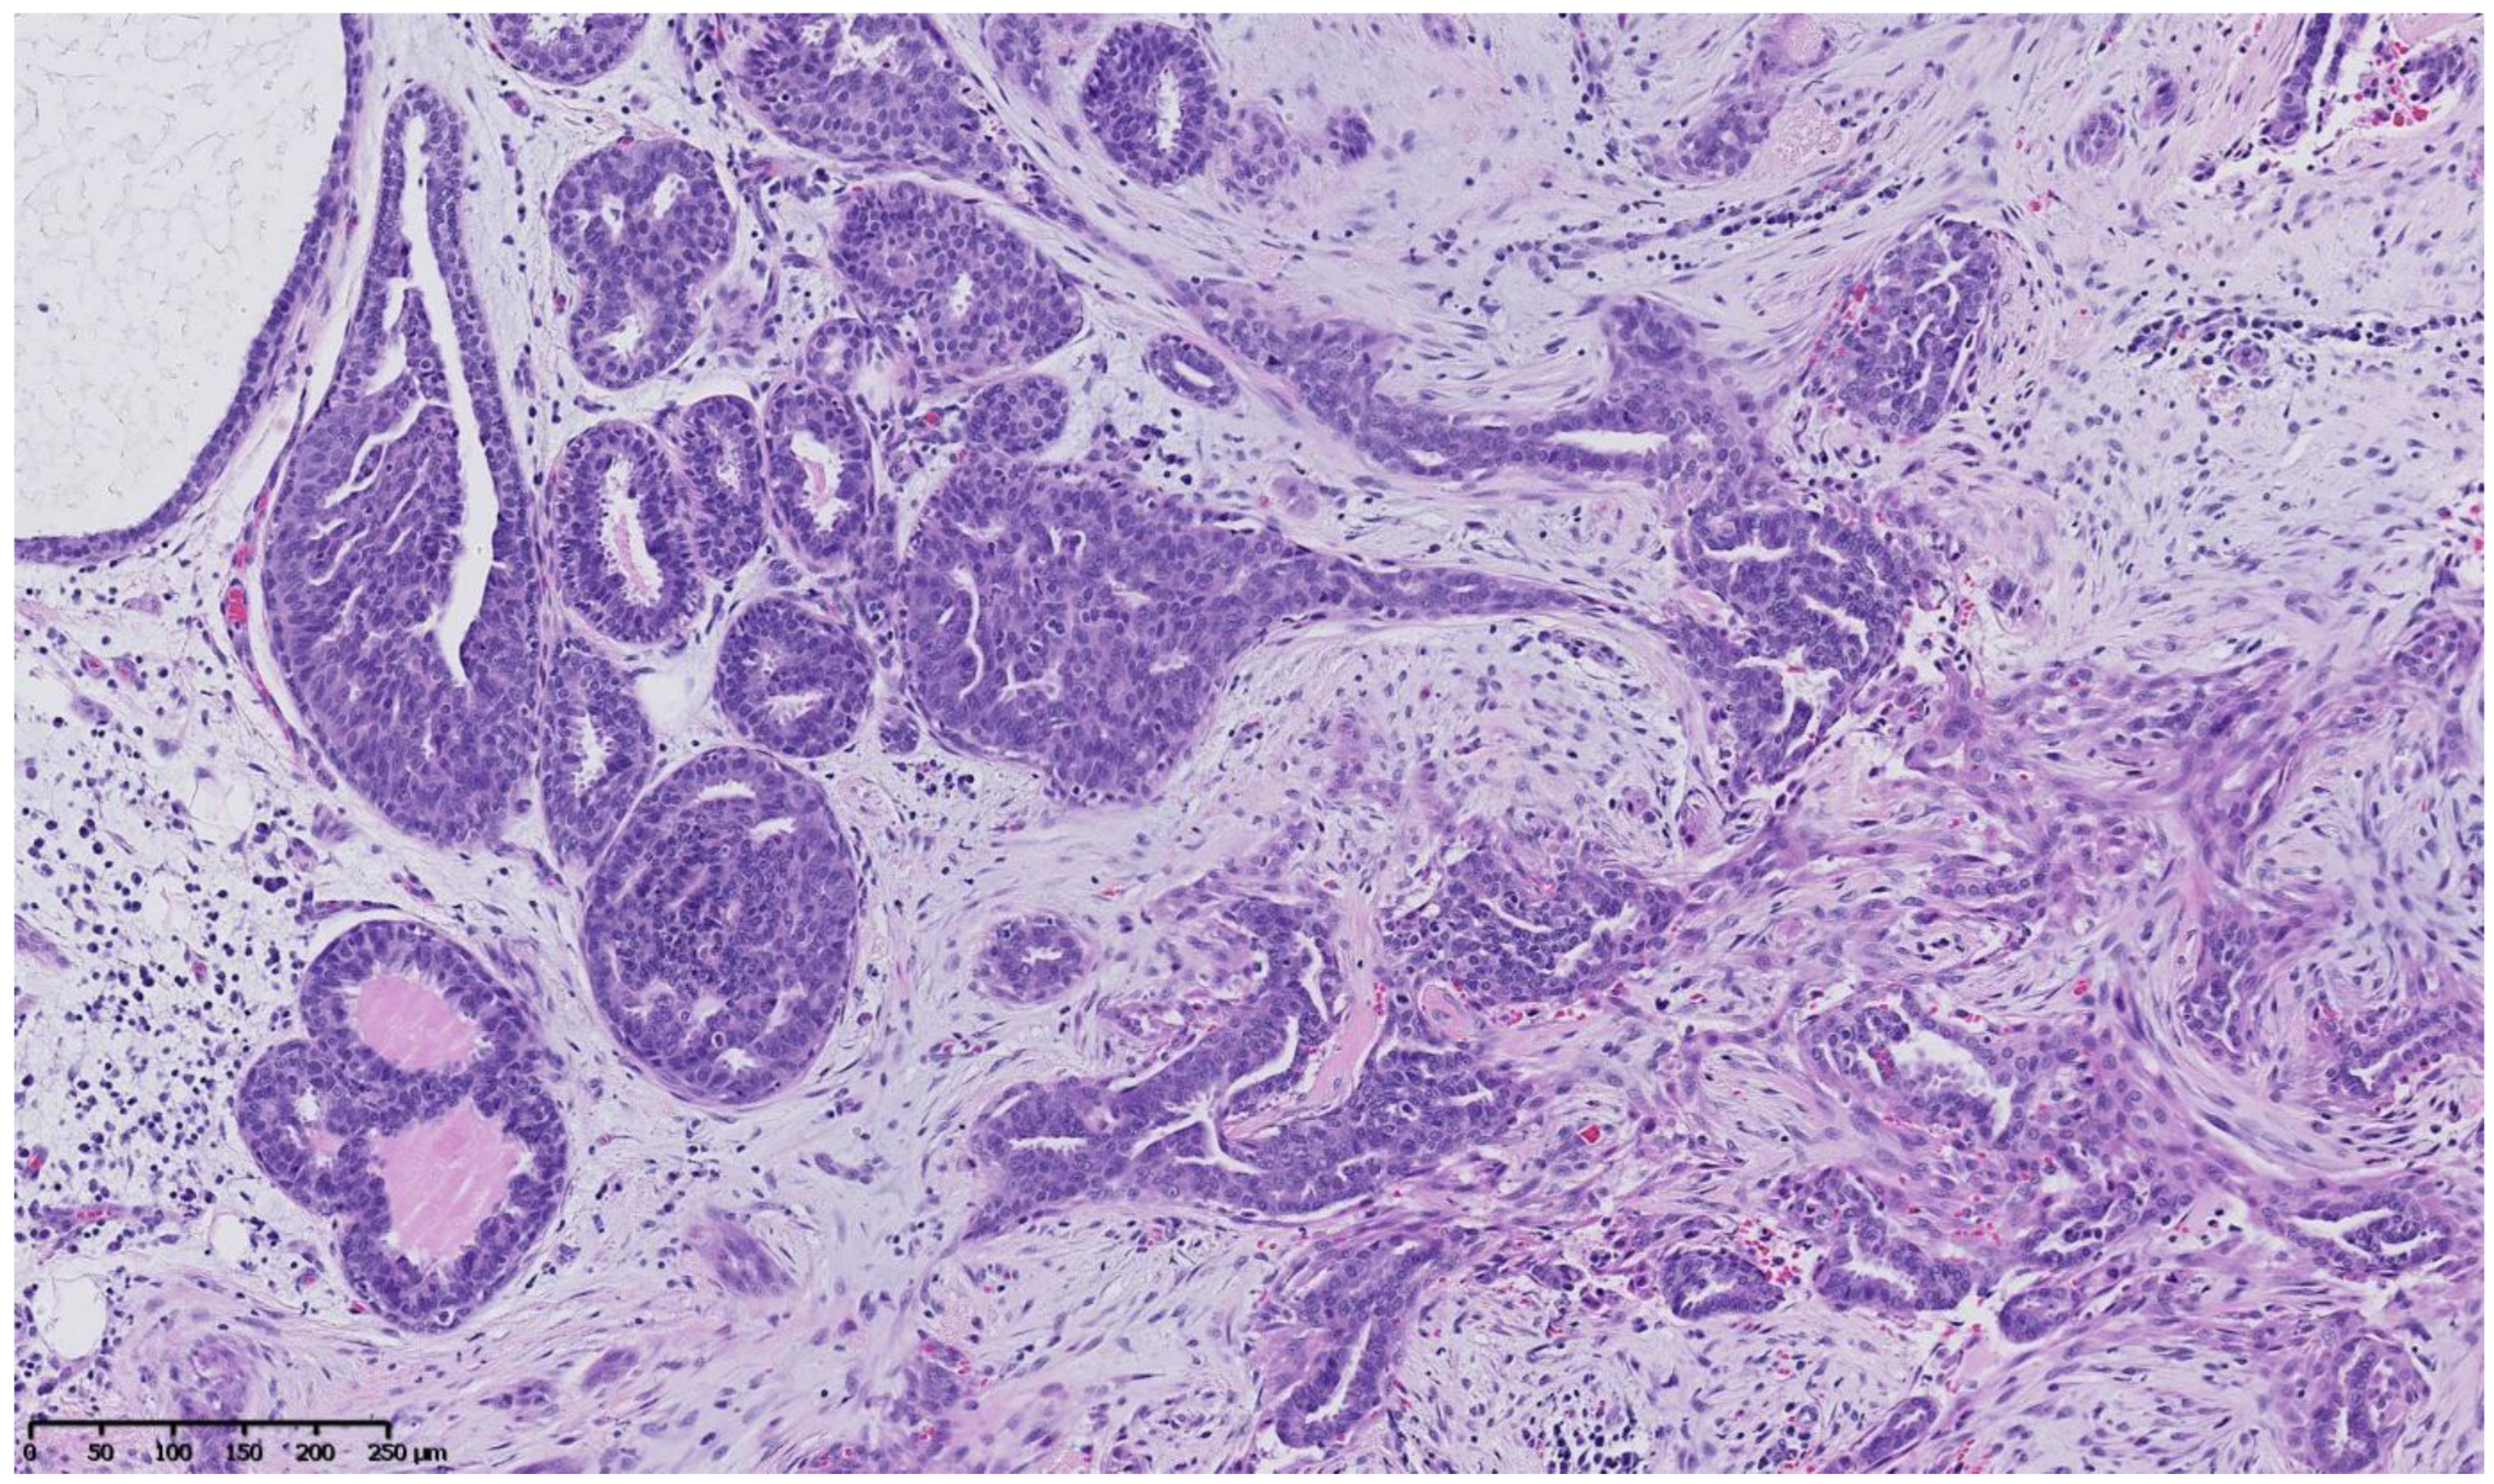

Figure 2, Figure 3, Figure 4, Figure 5, Figure 6 and Figure 7 describe a panel of different lesions observed in a patient treated for 2 years by natural estrogens and antiandrogens.

Figure 4.

Hematoxylin and eosin staining: at mid magnification, the ducts vary in size, and some look irregularly shaped and pseudo-invasive in the retracted fibrous stroma, whereas others are enlarged and contain an intra-ductal epithelial proliferation.